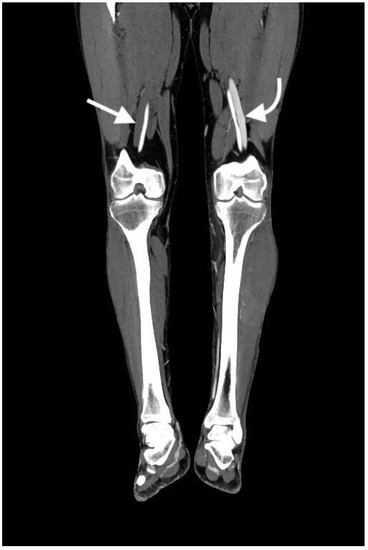

2.4.2. Arterial Occlusion or Stenosis